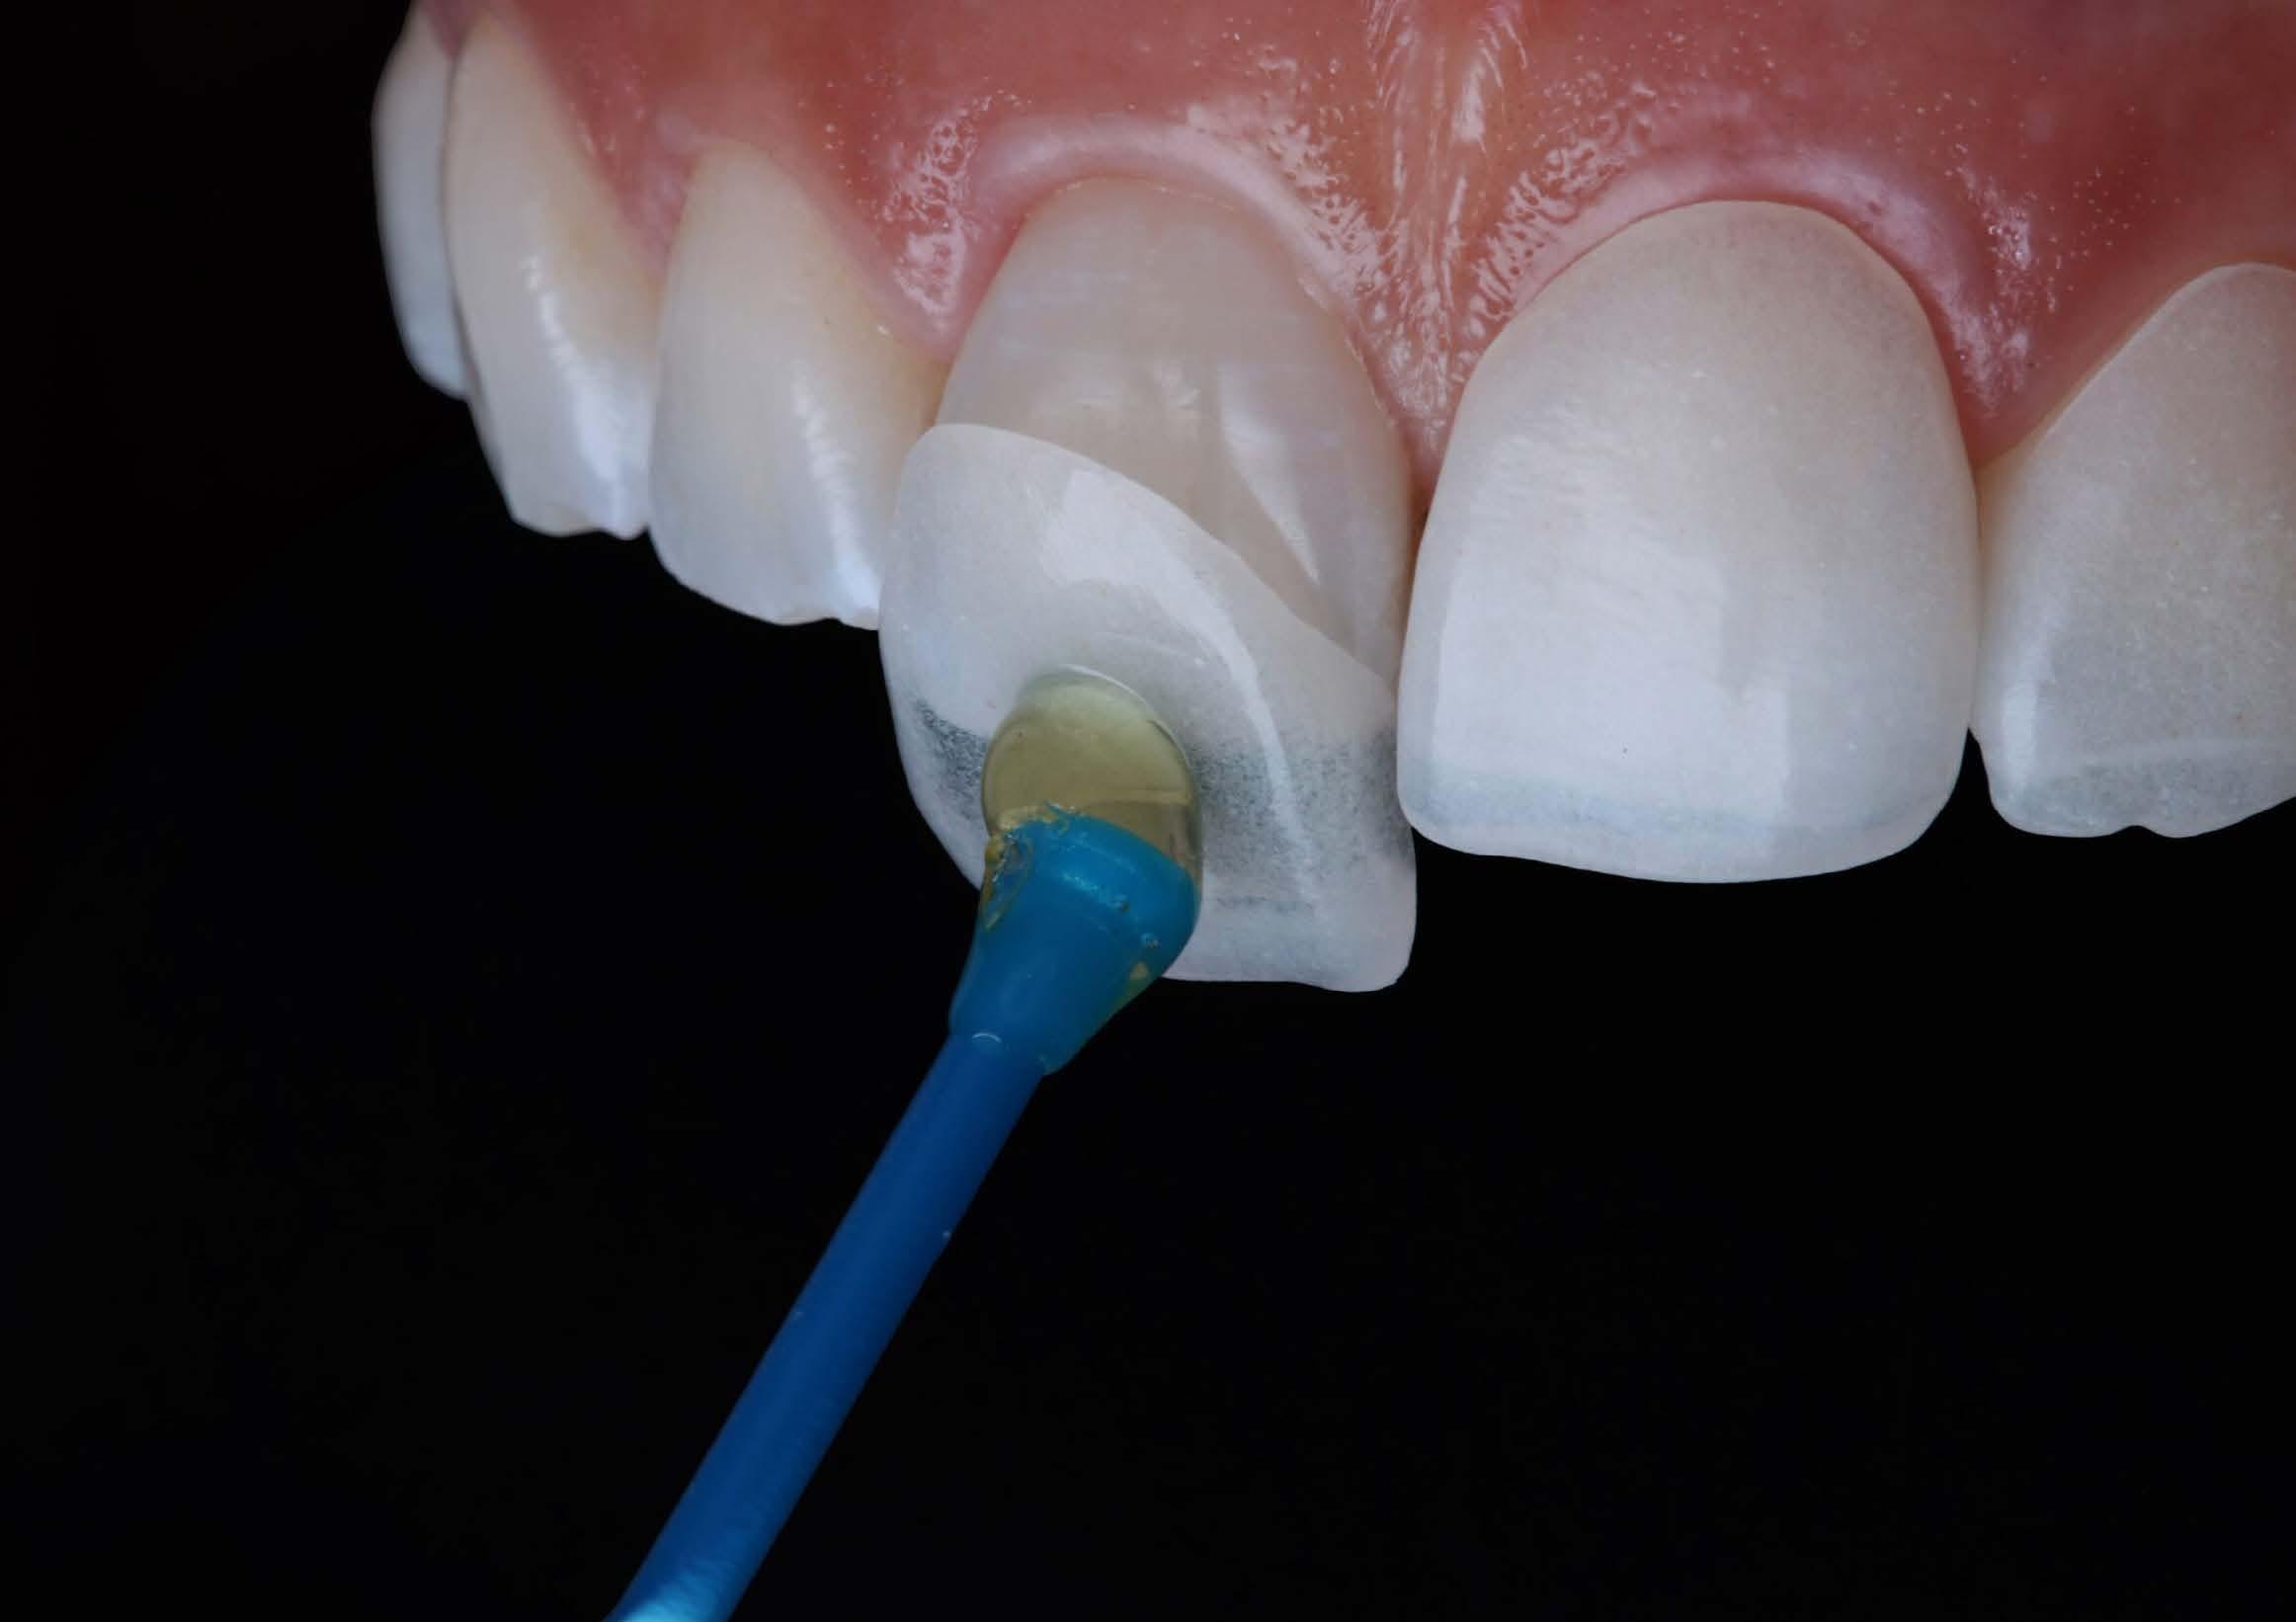

Based on the clinical and radiographic findings, tooth 22 was diagnosed as necrotic with a possibly infected root canal system (RCS), pulp canal calcification and primary acute apical periodontitis due to decay, cracks and restoration breaking down. An endodontic investigation procedure was planned to determine whether the 22 was suitable for further restoration. While the treatment was supposed to be straightforward initially, it progressed to become very complex surprisingly. This was due to separation of a size-10 H-file in the root canal of tooth 22.

The instrument separation was first noticed after taking the initial radiograph to establish the working length. It probably happened due to the patient biting inadvertently on the file during x-ray exposure. As our patient was a bruxer, his bite forced the file deeper in the

severely calcified root canal. The file was now firmly stuck inside the root canal. Despite trying to gently retrieve the file, it broke at junction of the cutting surface to the shank. Bypassing and/or retrieval procedures were planned and performed by using hand files, rotary files and Satelec ultrasonic tips in three different sessions, each one almost three hours long. Rotary files were used mainly as adjunctive instruments.

Taking advantage of rotary files made of a heat-treated alloy with minimal cutting efficiency, designed in a way to scrape rather than cut the dentin, enabled me to safely enlarge the space made by the hand files. This technique also participated in less frequency and chance of breaking more files next to the broken file.

Finally, the broken file segment was removed with braiding barbed broaches around the file. Notably, the patient patiently cooperated all throughout the treatment.

I had a thorough discussion with the patient about the reasons why this incident happened. Even though I could have simply pointed out a severely calcified root canal or a heavy bite to be responsible for the incident, I concluded that the patient’s occlusion should have been assessed carefully during case assessment in order to set preventive measures, which in turn could have potentially saved the patient and I from all the consequences.

Take home message - ALWAYS check your patient’s occlusion during the first examination/ consultation session. It will save you a lot of money!

Fig.1 File got stuck (22/09/2023) Fig.2 File fractured (22/09/2023)

Fig.4 Cut the file deeper (22/09/2023)

Bypassed to WL (12/10/2023)

And even deeper (12/10/2023)

Fig.3 Made space coronally (22/09/2023)

Fig.6 Rotary files used (12/10/2023)

Fig.8 Finally retrieved the file (12/10/2023)